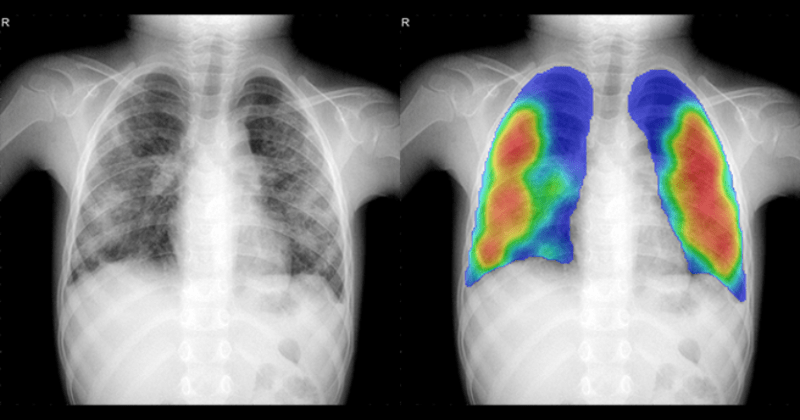

CAD4TB analysis of a child's chest X-ray, showing the original image alongside an AI-generated heat map highlighting lung abnormalities, Nigeria.

Chest X-rays with high CAD4TB scores were further evaluated by radiologists and clinicians to assess the likelihood of active TB.